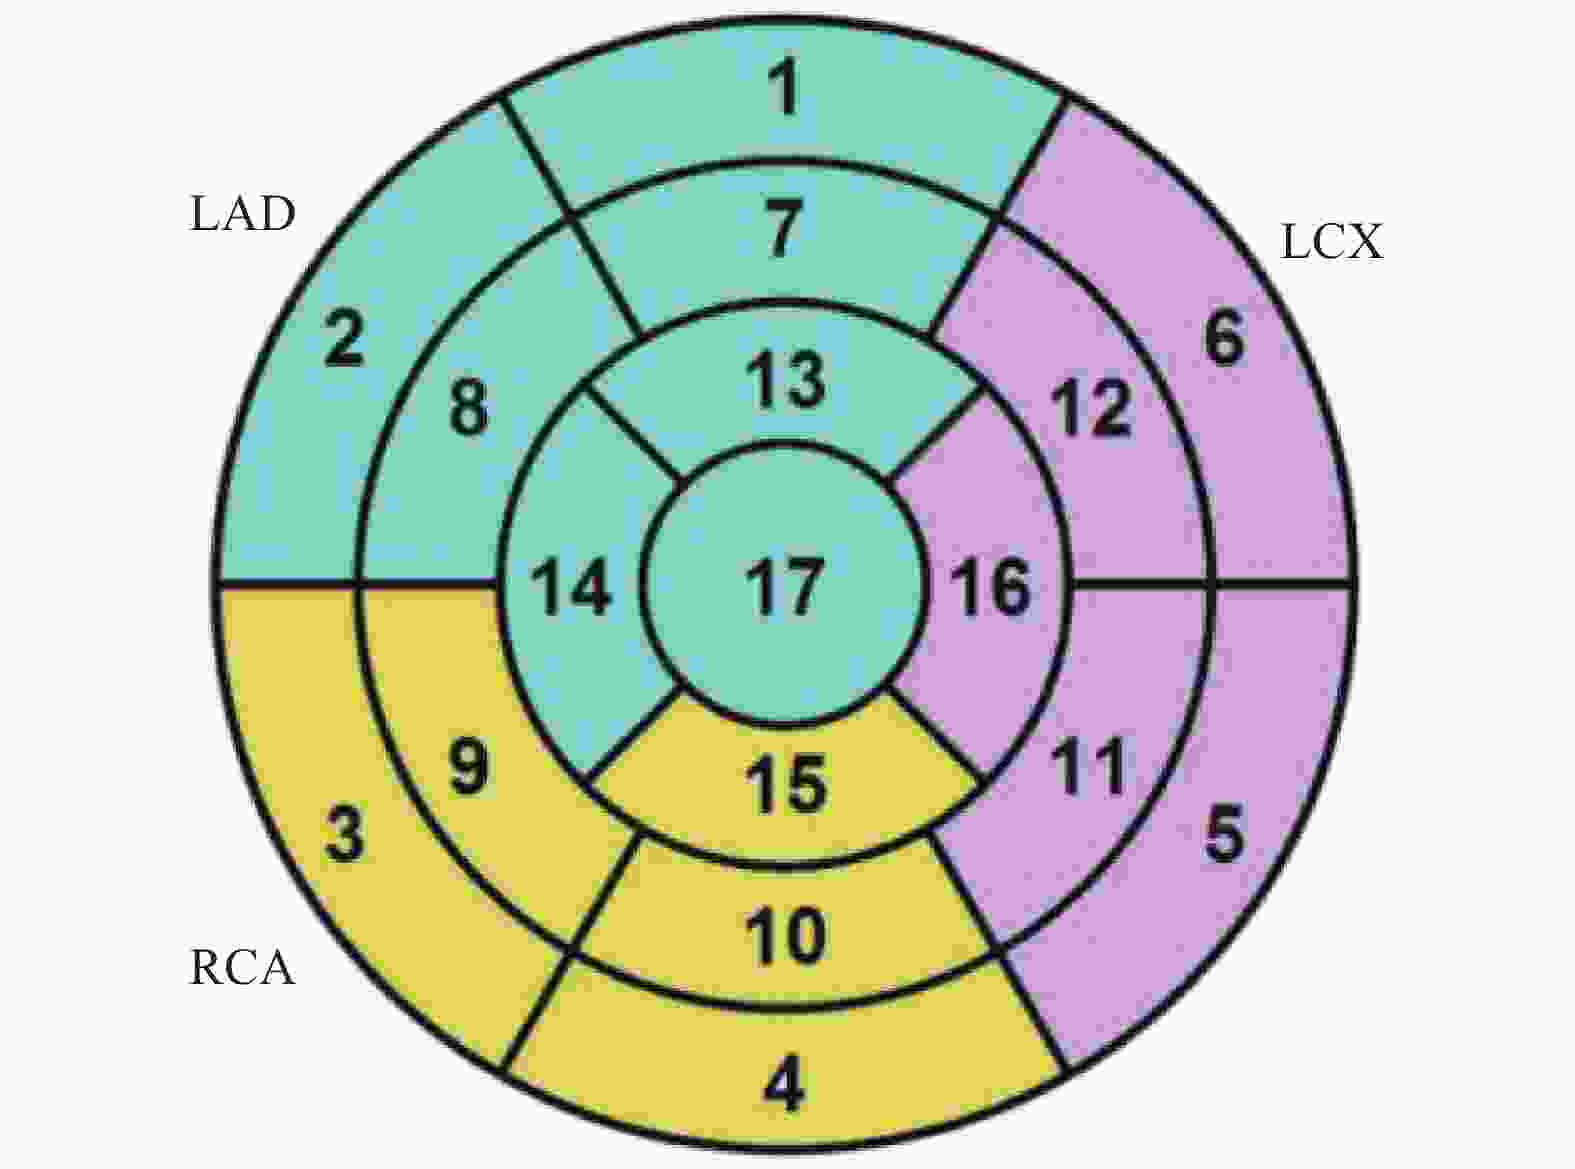

Table 9. Comparison of tpeak between the caIMR < 25 group and the caIMR ≥ 25 group[M(P25,P75)]

节段 caIMR<25组(n=24) caIMR≥25组(n=26) U/t P 1 20.50 (13.40,22.57) 36.35 (26.55,48.92) 124.000 <0.001* 2 15.30 (11.70,20.25) 31.00 (23.37,42.62) 81.500 <0.001* 7 21.65 (14.40,25.30) 34.95 (26.87,39.55) 4.438 <0.001* 8 22.00 (14.20,23.80) 35.05 (26.77,42.07) 103.500 <0.001* 13 19.50 (12.20,27.70) 29.90 (25.47,38.45) 155.000 0.001* 14 20.75 (12.50,29.55) 34.20 (25.02,42.17) 3.955 <0.001* *P < 0.05。 表 10 caIMR<25组与caIMR≥25组RSIpeak比较[M(P25,P75)]

Table 10. Comparison of RSIpeak between the caIMR < 25 group and the caIMR ≥ 25 group[M(P25,P75)]

节段 caIMR<25组(n=24) caIMR≥25组(n=26) U P 1 163.250 (106.525, 1099.375 )110.900 (90.225,136.425) 243.000 <0.001* 2 160.800 (123.600,232.725) 144.300 (106.750,997.725) 342.000 0.004* 7 182.700 (125.825, 1188.825 )125.550 (117.900,164.150) 259.500 <0.001* 8 142.000 (137.000,166.000) 159.600 (119.825, 1173.275 )287.000 0.253 13 207.250 (148.675, 1274.100 )189.700 (173.050,251.600) 310.000 0.001* 14 193.250 (164.475,221.300) 204.800 (149.125, 1187.375 )304.000 0.641 *P < 0.05。 表 11 caIMR<25组与caIMR≥25组Slopemax比较[M(P25,P75)]

Table 11. Comparison of slopemax between the caIMR < 25 group and the caIMR ≥ 25 group [M(P25,P75)]

节段 caIMR<25组(n=24) caIMR≥25组(n=26) U P 1 12.500 (8.000,68.775) 10.100 (6.700,12.100) 284.500 <0.001* 2 16.950 (9.800,30.275) 13.950 (8.650,63.550) 340.500 <0.001* 7 12.200 (9.825,14.750) 12.400 (8.650,64.350) 315.500 0.326 8 14.700 (11.325,16.100) 12.500 (8.775,59.350) 323.000 <0.001* 13 18.500 (13.975,36.400) 15.450 (10.850,91.625) 346.500 0.003* 14 17.900 (11.050,22.700) 16.900 (11.075,68.200) 316.500 0.001* *P < 0.05。 表 12 caIMR组与CMR组交叉表分析